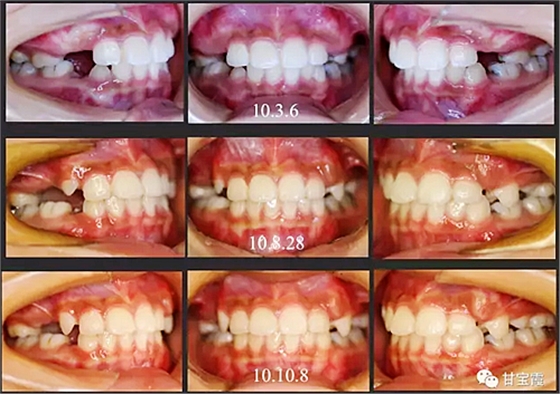

有一個七歲的小女孩,在替牙時媽媽發(fā)現(xiàn)孩子新長的牙不整齊,有一顆長到里面了,上下頜中線也不對稱,很著急就來到門診看牙。

經(jīng)過我臨床檢查和X線的診斷,決定早期干預(yù),每三個月定期復(fù)診檢查一次,并拔掉了幾個乳牙和四個恒牙,正畸專業(yè)叫序列拔牙。

經(jīng)過三年零九個月的看護(hù),最終戴上了固定矯治器,但是大家不難發(fā)現(xiàn),孩子的牙齒已經(jīng)排齊,上下中線也基本對齊,面型也好看多了,這樣矯正就變得簡單,療程自然縮短,孩子也不遭罪了。